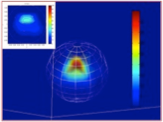

mOdélisation et oPTimisation de l’Irradiance dans les tissus biologiQUEs hétérogènes traités par Thérapie PhotoDynamique interstitielle

Modéliser pour optimiser le positionnement de fibres optiques en thérapie photodynamique interstitielle.

Partenaires: IECL, INSERM U703